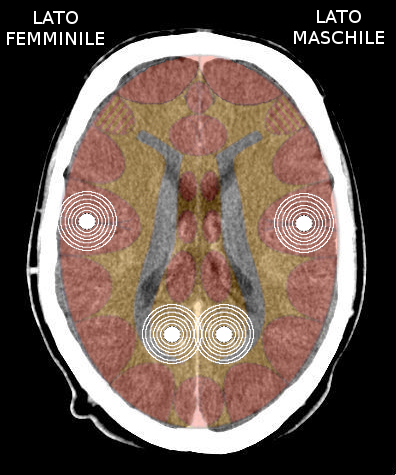

Possono esserci due o più costellazioni schizofreniche anche su livelli differenti (ad es. una costellazione corticale e una cerebellare) - I relè cerebrali: In una costellazione si possono avere:

- Un'attivazione in fase attiva ed una in crisi epilettoide

- Entrambe le attivazioni in fase attiva

- Entrambe le attivazioni in crisi epilettoide